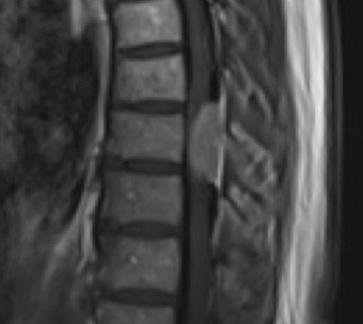

Preoperative MRI T1w demonstrating a large enhancing tumor with severe cord compression

Preoperative MRI T1w demonstrating a large enhancing tumor (red arrow) causing severe cord compression and displacement (blue arrow)

This is a 55-year-old female with no past medical history who presented electively with a 10 month history of progressively worsening mid back pain radiating across the chest, and gait disturbance. Pain was especially worse at night and when laying flat. Her exam was pertinent for severe ataxia when ambulating, and elevated deep tendon reflexes in the lower extremities. She had severe and debilitating symptoms, as demonstrated by her Visual Analog Scale (VAS) and Oswestry Disability Index (ODI) of 9/10 and 64/100, respectively. MRI of the thoracic spine with and without contrast demonstrated a large intradural extramedullary homogenously enhancing mass at T8, resulting in near obliteration of the spinal canal and severe cord compression. She was referred to Dr. Xavier Gaudin for neurosurgical management.